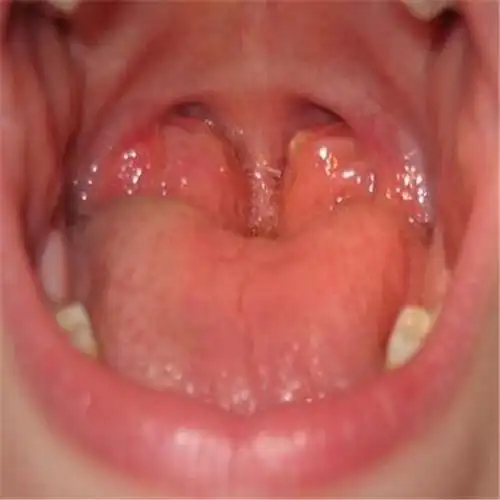

儿童扁桃体腺样体肥大需要手术吗

扁桃体肿大

扁桃体肿大图片50

扁桃体二度肿大. 没症状. 之前急性咽喉炎. 吃药好了.